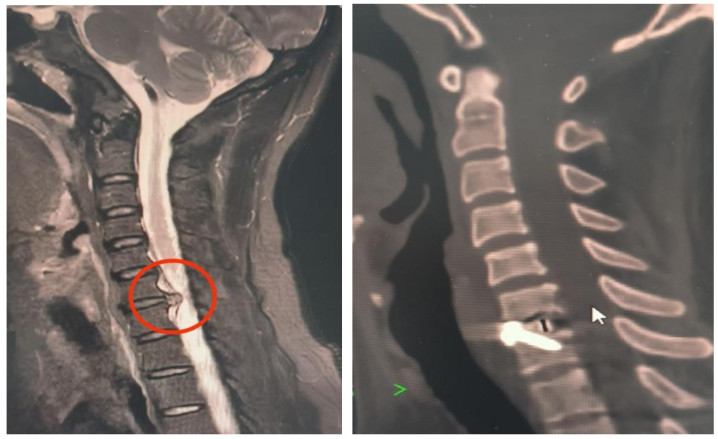

国产原创技巧+中医脾气疗法 HAI住院后,姜铁斌副主任医师团队就为HAI进行了中西医联结的详备诊疗,各项搜检截止联结其舌红苔厚白、痛有定处的症状,中医辨证为“项痹(气滞血瘀证)”,西医确诊为“神经根型颈椎病”。团队决定遴荐该院黎庆初诠释注解团队研发的荣获广东省技巧发明奖一等奖的国产革命技巧——LUSE单通说念软质内镜技巧来实施手术。 12月18日,姜铁斌副主任医师主刀为HAI进行了“LUSE下颈椎前路C6/7椎间盘切除+椎间植骨会通内固定术”。手术全程仅用数十分钟,出血仅10ml。 “西医除病灶、中医调根底,是本次休养的亮点。”姜铁斌先容,针对HAI的气滞血瘀证,照应团队同步入手中医抽象珍视决策:葫芦灸温通经络、散寒止痛,火龙罐集按摩、艾灸、刮痧于一体,在风池、肩井等穴位精确施治,加快颈肩部血液轮回,再辅以强筋壮骨丸补益肝肾,变成“微创休养+中医康复”的闭环。